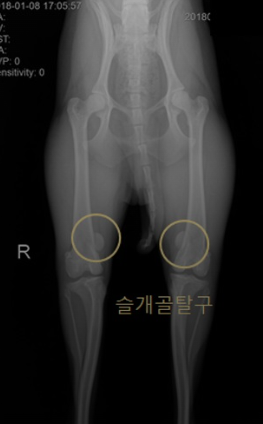

슬개골 탈구란?

슬개골 탈구는 강아지의 무릎을 덮고 있는 작은 뼈인 슬개골이 원래 위치에서 벗어나는 현상을 말합니다. 슬개골은 무릎 관절의 움직임을 돕고 보호하는 역할을 하지만, 유전적인 요인이나 외상으로 인해 슬개골이 무릎 안쪽이나 바깥쪽으로 탈출하게 됩니다. 이때 슬개골 주변의 인대나 근육이 손상되고, 관절염이나 십자 인대 파열과 같은 다른 질환을 유발할 수 있습니다.

슬개골 탈구는 주로 소형견에게 흔하게 발생하는 질환으로, 포메라니안, 치와와, 말티즈 등이 취약합니다. 암컷보다 수컷이 잘 걸리며, 양쪽 다리에 동시에 발생할 수도 있습니다. 슬개골 탈구의 증상은 다음과 같습니다.

슬개골 탈구는 진행 정도에 따라 1기부터 4기까지 나뉘며, 1기는 가벼운 탈구로 슬개골이 자연적으로 제자리로 돌아가고, 4기는 심한 탈구로 슬개골이 제자리로 돌아가지 않고 통증이 심해집니다. 슬개골 탈구의 진단은 병원에서 촉진 검사나 X-선 검사를 통해 할 수 있습니다.